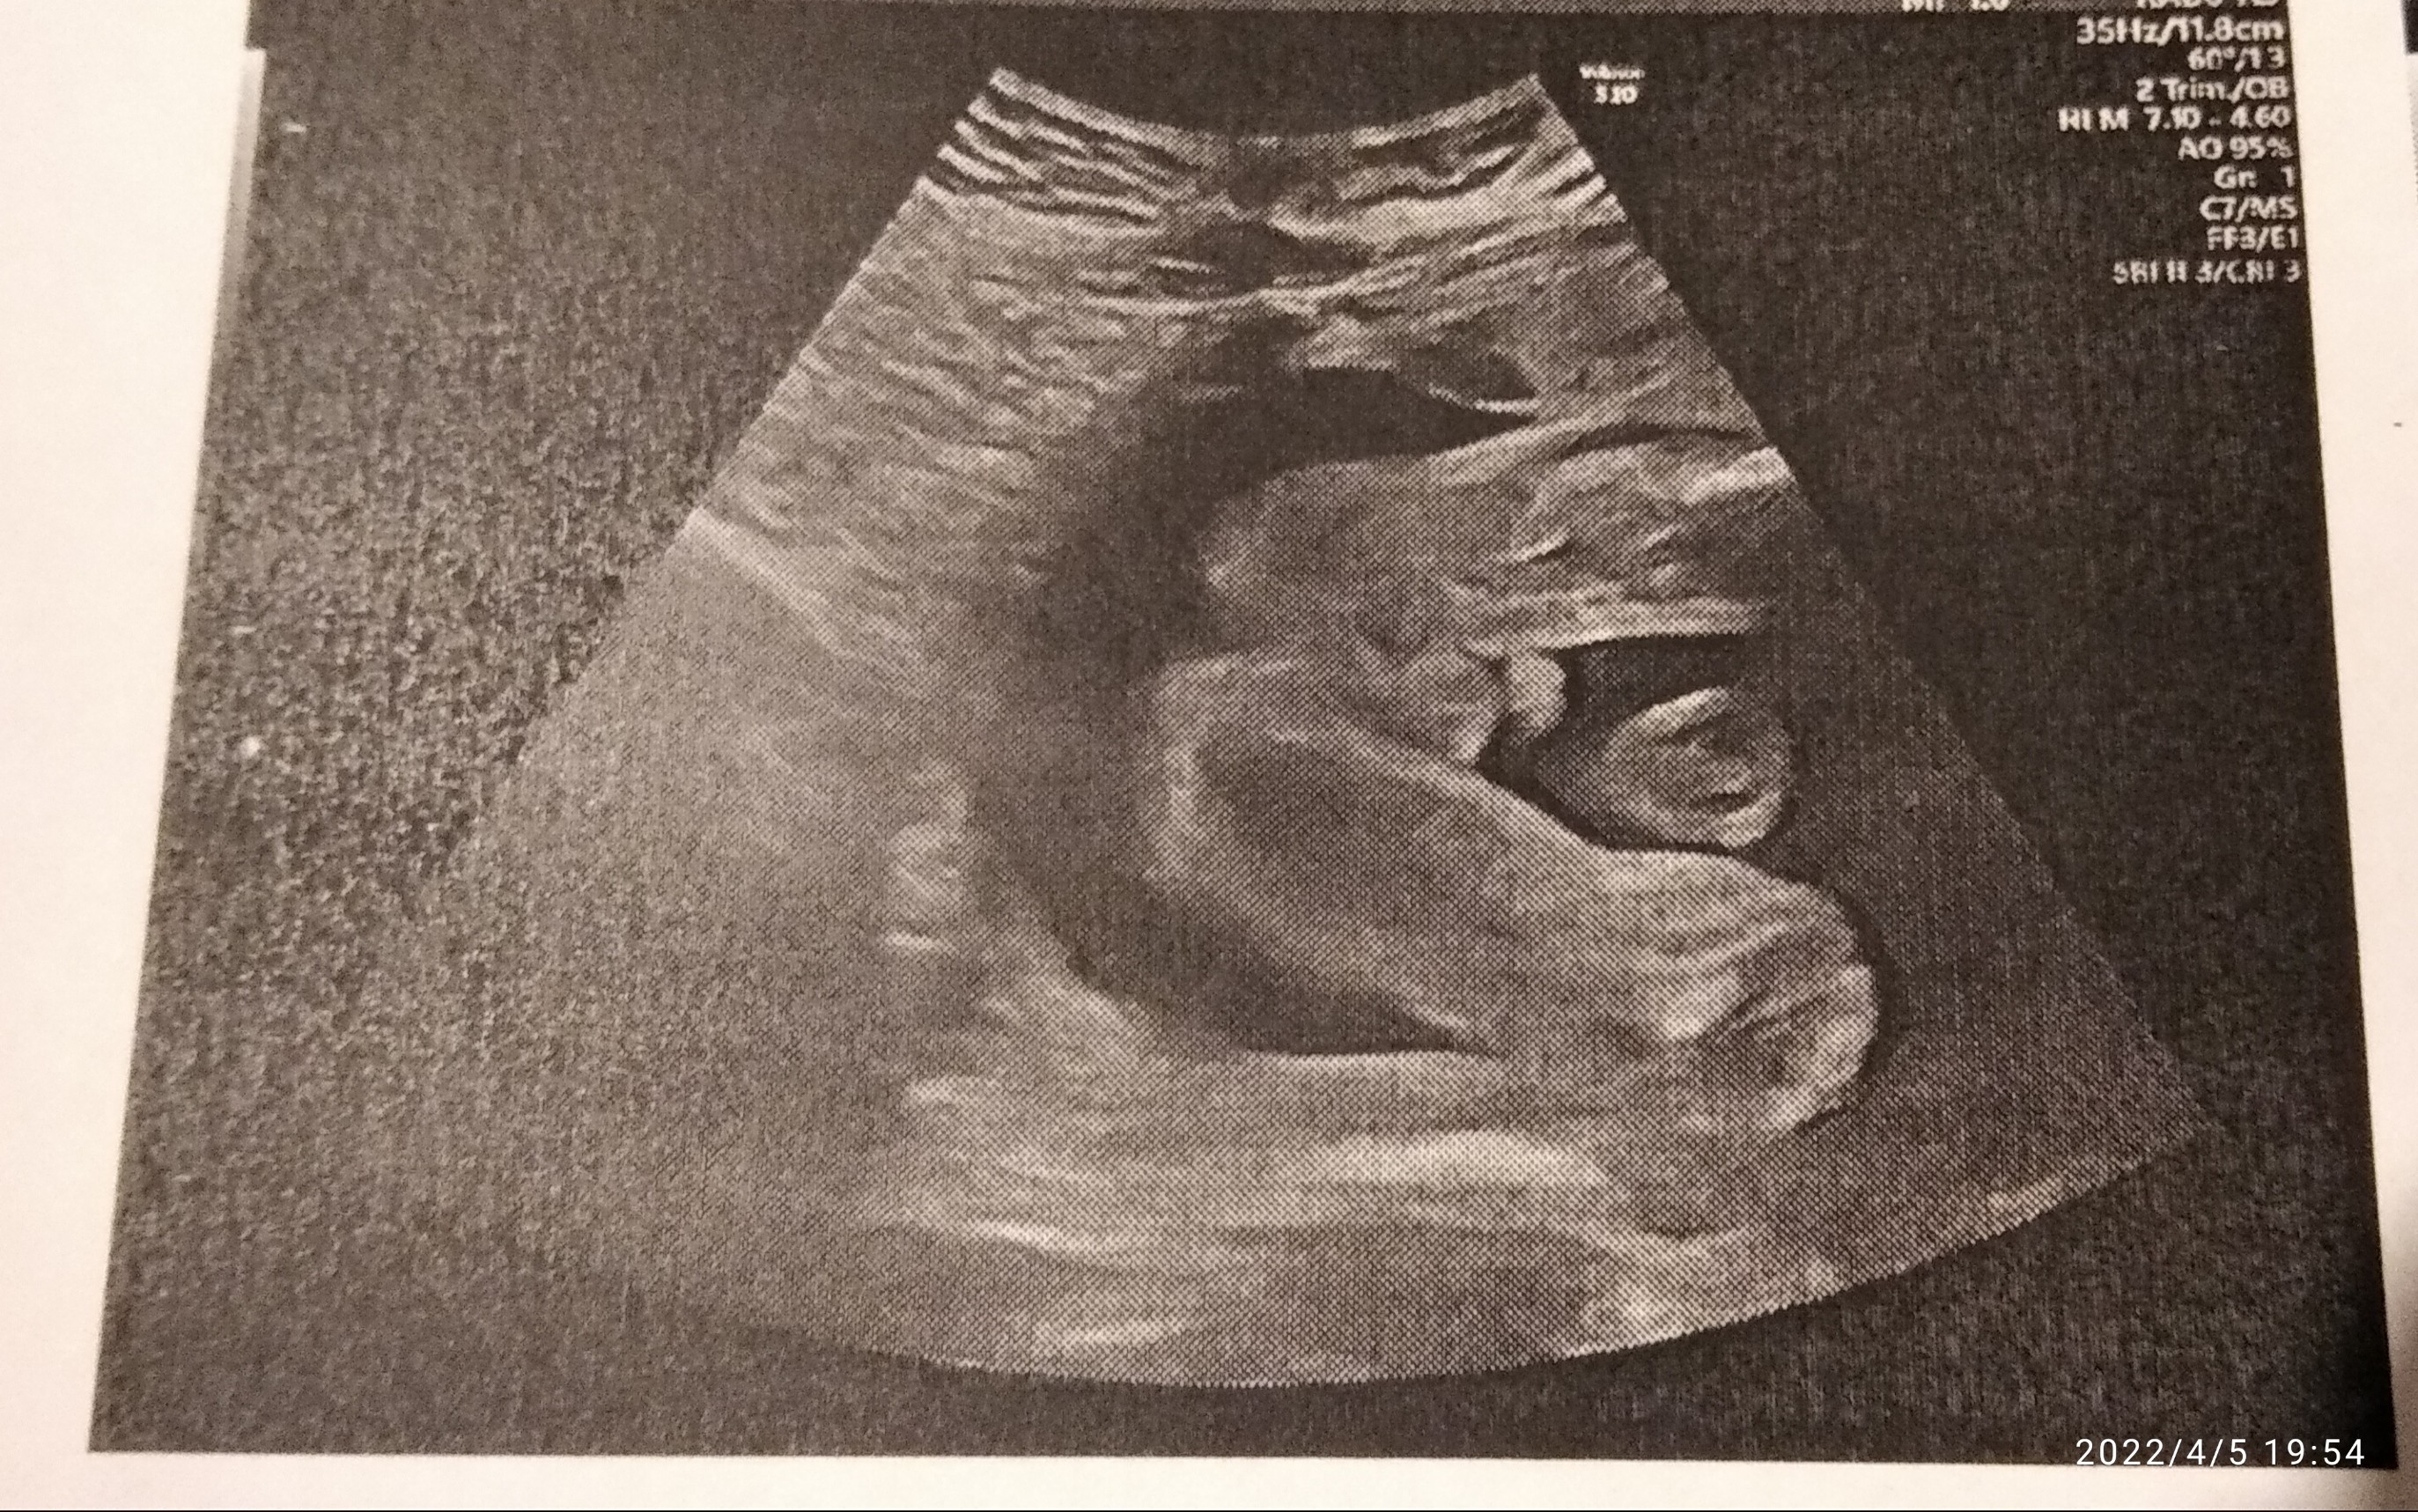

Pokaże Ci jak wygląda zdjęcie mojego dzidziusia z tej perspektywy, mam mieć synaOk, No zobaczymy co się urodzi za ok 8 tygodni. Zastanawia mnie ta ciemna kropka w kroku.

A który to tydzień u Ciebie?Pokaże Ci jak wygląda zdjęcie mojego dzidziusia z tej perspektywy, mam mieć syna![]()

Według miesiączki 23, a według USG 24A który to tydzień u Ciebie?